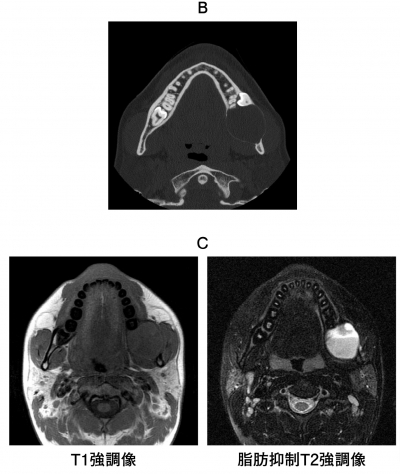

24歳の男性。下顎左側大臼歯部の腫脹を主訴として来院した。同部に境界明瞭な無痛性の腫脹を認める。初診時のエックス線写真、CT及び MRI T1強調像と脂肪抑制T2強調像を別に示す。